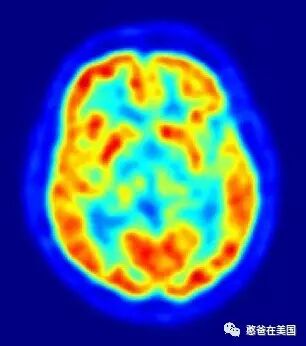

在研究开始之前,他们进行了一系列的心理旋转任务来测试孩子们的空间思维能力。孩子们必须观察字母类的图案,并确定看到的是否是翻转(“镜像”)或仅仅是旋转。当完成任务后,他们的速度和准确度都会被记录下来。此外,研究者通过核磁共振测试了他们的大脑活动。

孩子们被根据性别、年龄、数学测试成绩、父母的教育水平以及之前的测试情况被平均地分配到了两组,保证实验前两组内的孩子在智力和空间思维上基本没有区别。但在随后的5分钟、30分钟的游戏试验中,差距开始出现了,当过了12天之后,她们发现孩子出现了显著的变化。

当实验结束后,研究人员重新测试孩子们的心理旋转能力,他们发现玩乐高玩具的一组孩子在速度和准确性方面得到了显著的提高。此外,他们的大脑扫描图谱显示,在与空间处理有关的大脑区域变得更加活跃。而这个区域越活跃,孩子们更有可能以一种新的方式来解决心理旋转问题。

最后,Newman教授得到了一组结论:玩乐高类拼搭积木对儿童的智力提升很有帮助,特别是空间感提升效果非常明显。